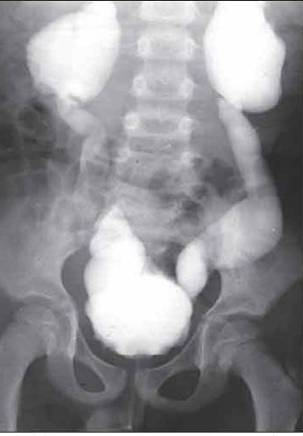

Екскреторна урографія хворого з двостороннім обструктивним мегауретритом

На екскреторній урографії ми спостерігаємо збільшення мисочок, розширення сечоводів, і змінену форму сечового міхура. Стінки якого мають бугристу, нерівну поверхню.